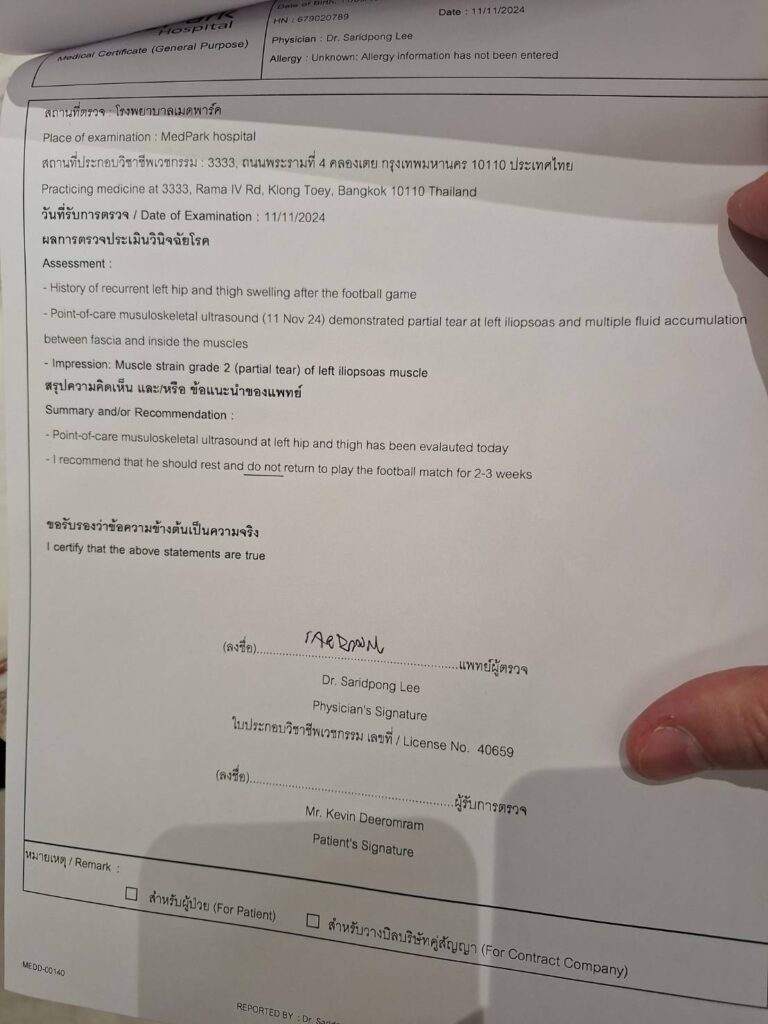

ล่าสุด มาซาทาดะ อิชิอิ หัวหน้าผู้ฝึกสอนทีมชาติไทย และ นายแพทย์ ภคภณ อิสรไกรศีล ในฐานะแพทย์ประจำทีม ได้ประเมินอาการร่วมกับผลตรวจสแกนที่โรงพยาบาล พบว่ามีการเจ็บที่กล้ามเนื้อสะโพก และ มีเลือดคั่ง ต้องใช้เวลาในการพักฟื้น 1-2 สัปดาห์ และ มีความเสี่ยงที่จะบาดเจ็บเพิ่มเติมรุนแรงมากขึ้น ก่อนที่ มาซาทาดะ อิชิอิ และ นายแพทย์ ภคภณ อิสรไกรศีล จะตัดสินใจร่วมกันให้ เควิน ดีรัมย์ ถอนตัวจากทีมชาติไทยชุดนี้ เพื่อป้องกันความเสี่ยงในการบาดเจ็บรุนแรงมากขึ้น